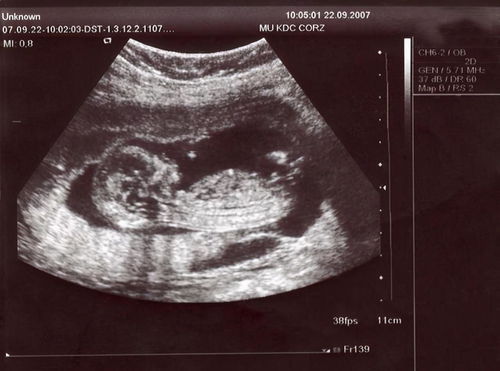

懷孕早期過程中做B超是不必要的,并且做了B超也僅僅是檢查一下是否發(fā)生了宮外孕等比較明顯的癥狀,這個時期醫(yī)院的醫(yī)生也會不建議孕婦做B超,所以請那些急切想知道自己孩子情況的女性再耐心等幾周,再去做B超也為時不晚。

1.早期做B超需要在膀胱里積聚一定量的小便才能看得清楚,所以要提前憋尿。

過了孕3個月寶寶長大了就不用憋尿了,隨去隨做。 2.不要餓著肚子做B超,特別是孕中晚期,肚子餓的話寶寶不配合,有些數(shù)據(jù)看不清楚,無法測量,或者測出來的數(shù)據(jù)不準確。